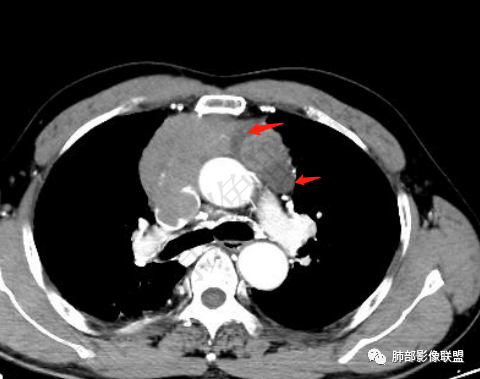

2.上纵隔增宽并见不规则块影,密度不均,轻度不均匀强化,隐约见液化密度区。

病灶边界不清,轻度分叶,后方部分紧密包绕升主动脉且侵入上腔静脉及左无名静脉末端,相应上腔静脉及左无名静脉管壁不完整。

▲上腔静脉内瘤栓

▲病灶骑跨在主动脉前缘,主动脉包绕

▲左侧边缘有强化的病灶,似乎符合坏死或囊变、或有粘液类物质。内部似有裂隙、坏死。坏死边界偏清。

晨读,老年男性,面部肿胀1月余。前纵隔肿块,边缘膨隆,见分叶,整体较均匀强化,内见小坏死,侵犯周围大血管,考虑恶性,胸腺癌可能性大。

面部肿胀(腔静脉阻塞综合征),前纵隔实性肿块,密度均匀,分叶,病灶内多个低密度区,与腔静脉分界不清晰,增强病灶轻度强化,肺门,纵膈淋巴结增大,胸腺癌?